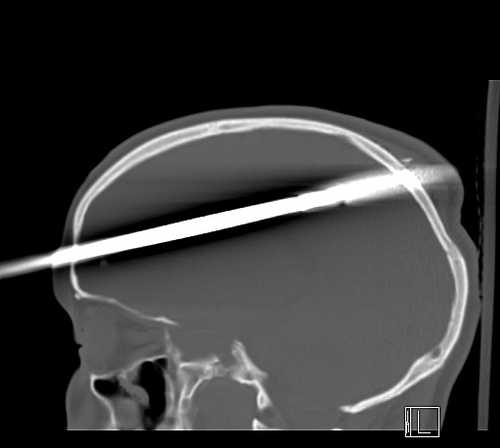

Florida teen recovering after being shot through head with spear

A FLORIDA TEENAGER is recovering in hospital after he was accidentally shot through the head with a spear by his friend during a fishing trip.

Doctors at the Jackson Memorial Hospital’s Ryder Trauma Center said yesterday that it took three hours to remove the spear from the 16-year-old’s brain.was rushed to hospital earlier this month with about 36 inches (3 feet) of spear protruding from his head. The projectile was accidentally fired by his friend as he was loading a spear gun.

The spear entered his forehead about two inches above his right eye and went through the back of his skull. Part of the visible section of spear was cut off to allow the teen to undergo cranial scans.

Doctors at the Jackson Memorial Hospital’s Ryder Trauma Center said yesterday that it took three hours to remove the spear from the 16-year-old’s brain.

The spear passed through the right hemisphere of his brain, missing major blood vessels, and doctors believe he could make a close to full recovery, ABC News reports. Although he does not remember the incident, the teenager has woken from his surgery and has spoken a few words.